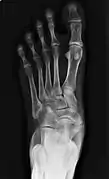

From left to right: Type 1, 2 and 3

Cornuate navicular bone